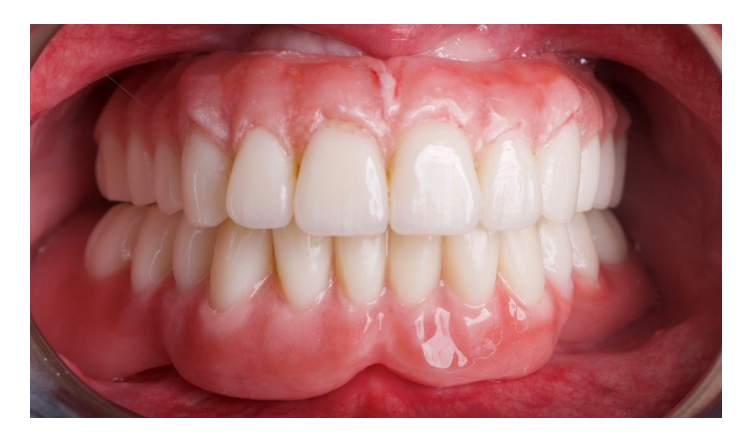

Ниже представлен объяснительный клинический случай. 62-летняя женщина обратилась за вторым мнением из-за существующих съемных частичных протезов, закрепленных на оставшихся естественных элементах, которые были установлены несколько месяцев назад. При клиническом и рентгенологическом обследовании пациентка предъявила основные жалобы на подвижность зубов, кровоточивость десен, боль, дискомфорт, плохую функцию и неэстетичный внешний вид (Рисунки 1 и 2).

После этого эстетическая примерка была снята. Четыре новые скан-аналоги были подключены к временным абатментам и отсканированы вне рта пациента с помощью обычного экстраорального сканера (Рисунок 21). Прежде чем была изготовлена окончательная CAD/CAM конструкция, клинически и радиографически была протестирована радиопрозрачная алюминиевая конструкция. После этого было выполнено перекрестное монтаж окончательной реставрации (позиция имплантата) с функционализированной временной реставрацией, а также с оригинальным планом. На следующем приеме титановая CAD/CAM конструкция была протестирована в рту пациента. В конце концов, была доставлена фиксированная, удерживаемая винтом, имплантоподдерживаемая реставрация, изготовленная из титана, с композитом в качестве облицовочного материала (Рисунки 22–24). Композит был выбран из-за своей прочности и способности к поглощению ударов. Лингвализированный окклюзия была спроектирована для всех окончательных реставраций, с использованием анатомических зубов для верхнего протеза и модифицированных неанатомических или полуанатомических зубов для нижних протезов.